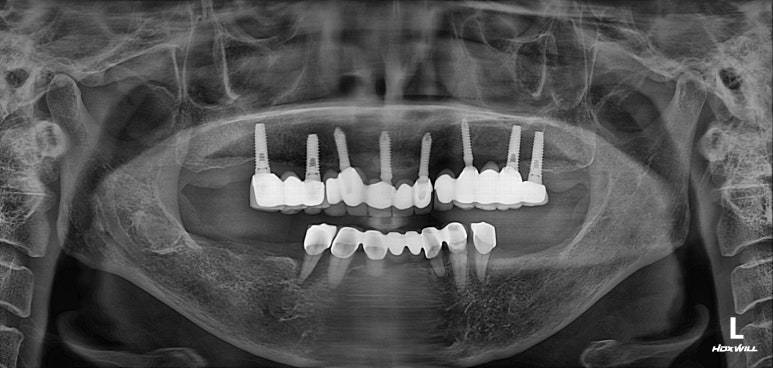

아래 틀니를 끼지 않은 상태에서 초진 정면 사진입니다.

기존에 치료받으신 임플란트의 metal 부분이 조금 비추긴 하나, 전체적으로 나쁘지 않습니다.

잘 보시면 아래턱의 맨 끝 치아 두개는 유독 치태가 많이 쌓여있고, 그 앞 치아들로부터 떨어져있는 것을 보실 수 있습니다.

화살표 표시해둔 두 개의 아래턱 작은 어금니는, 아래 부분틀니의 고리가 걸리는 치아입니다.

처음 아래 부분틀니를 제작할 당시에 여러개의 치아를 보철물로 묶어서 제작해드렸어야 하는데, 보시다시피 single crown으로 제작되어있는지라 성인 여성의 저작력을 견디지 못하고 만성치주염으로 흔들거리는 상태가 되었죠... 보면 치과용 파노라마 사진에서 두 치아 주변으로 까맣게 잇몸뼈 소실이 관찰됩니다.

위턱은 임플란트로 어느 정도 치아 자리가 채워져 있는 모습이지만, 아래턱은 어금니가 상당히 많이 없네요.